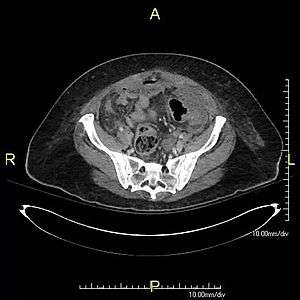

| Stercoral perforation CT cine clip | |

Stercoral perforation is the perforation or rupture of the intestine's walls by its internal contents, such as foreign objects, or, more commonly, by hardened feces (fecalomas) which may form in long constipations or other diseases which cause obstruction of transit, such as Chagas disease, Hirschprung's disease, toxic colitis and megacolon.

Stercoral perforation is a very dangerous, life-threatening situation, as well as a surgical emergency, because the spillage of contaminated intestinal contents into the abdominal cavity leads to peritonitis, a rapid bacteremia (bacterial infection of the blood), with many complications.